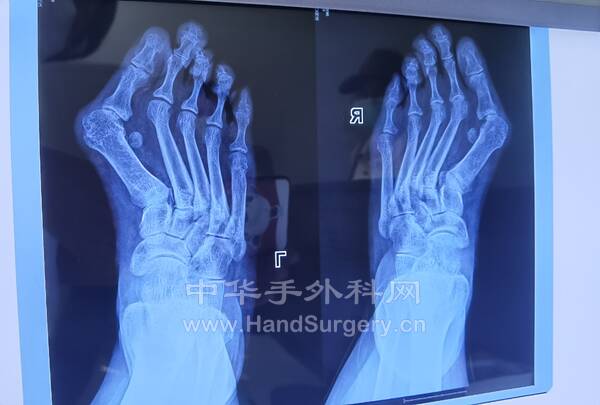

拇趾Chevron+Akin/Scarf+Akin/横行截骨+Akin.第2.3.4趾行Weil手术(图2,3)